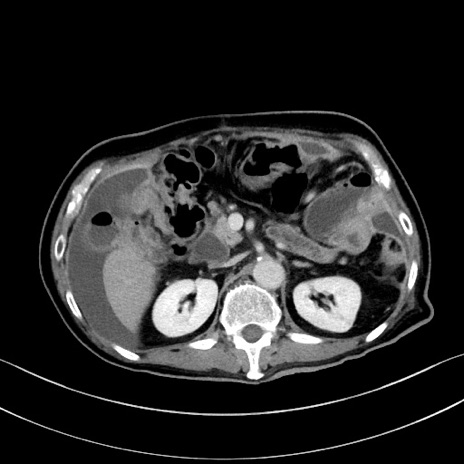

冠状断像

【症例】60歳代男性

【主訴】嘔吐

【現病歴】胃癌にて胃全摘後。食思不振が悪化し、夜中に嘔吐することがある。

【既往歴】胃癌、胃全摘、脾摘、胆摘後

【データ】WBC 5900、CRP 10.56